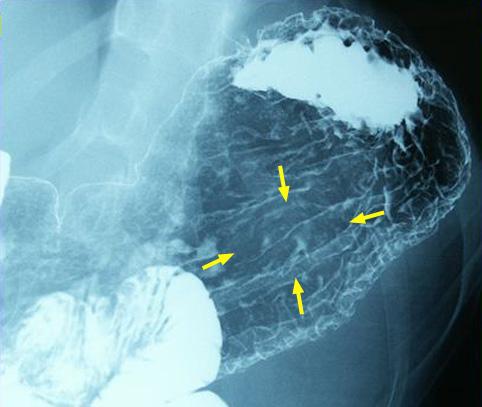

clasificación del pacienteTumor Maligno del Sistema Linfático/Linfoma Maligno

parte(separada por órganos)estómago(región)/cuerpo

método de exámenRayos X

clasificación ectoscópica de tumoresTipo 1(Tipo protuído)/

diámetro mayor del tumor35 - 40

grado de penetraciónmp